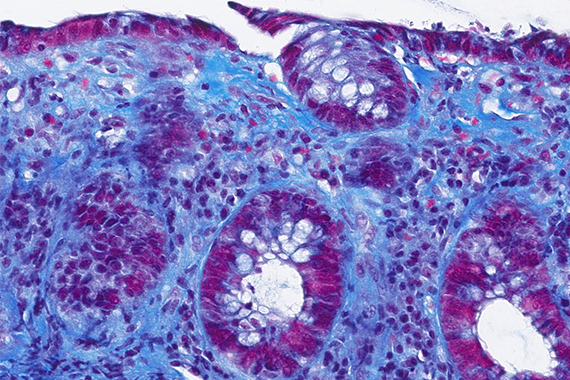

Colon biopsies in a 87 year-old female with chronic watery diarrhea.

Collagenous colitis with giant cells.

An 87-year-old woman presented with chronic, non-bloody, watery diarrhea and underwent colonoscopy, which revealed no endoscopic abnormalities. Biopsies were taken.

Histology of several colonic sites showed a thickened subepithelial collagen band (>10 μm), predominantly beneath the superficial epithelium but also surrounding the crypts (Panel A). Surface epithelial injury was also observed, with focal mucin depletion and detachment of superficial epithelial cells (Panel B). Lamina propria showed increased cellularity, with lymphocytic and plasmocytic infiltration, along with numerous giant cells (Panel C). There was no crypt architectural distortion. The collagen deposition was highlighted by Masson’s trichrome stain (Panel D) and strongly by tenascin immunohistochemistry (Panel E).

Histological variants of both collagenous and lymphocytic colitis have been described, including collagenous colitis with giant cells. In this variant, multinucleated giant cells are abundant and scattered throughout the lamina propria, with no apparent prognostic value.